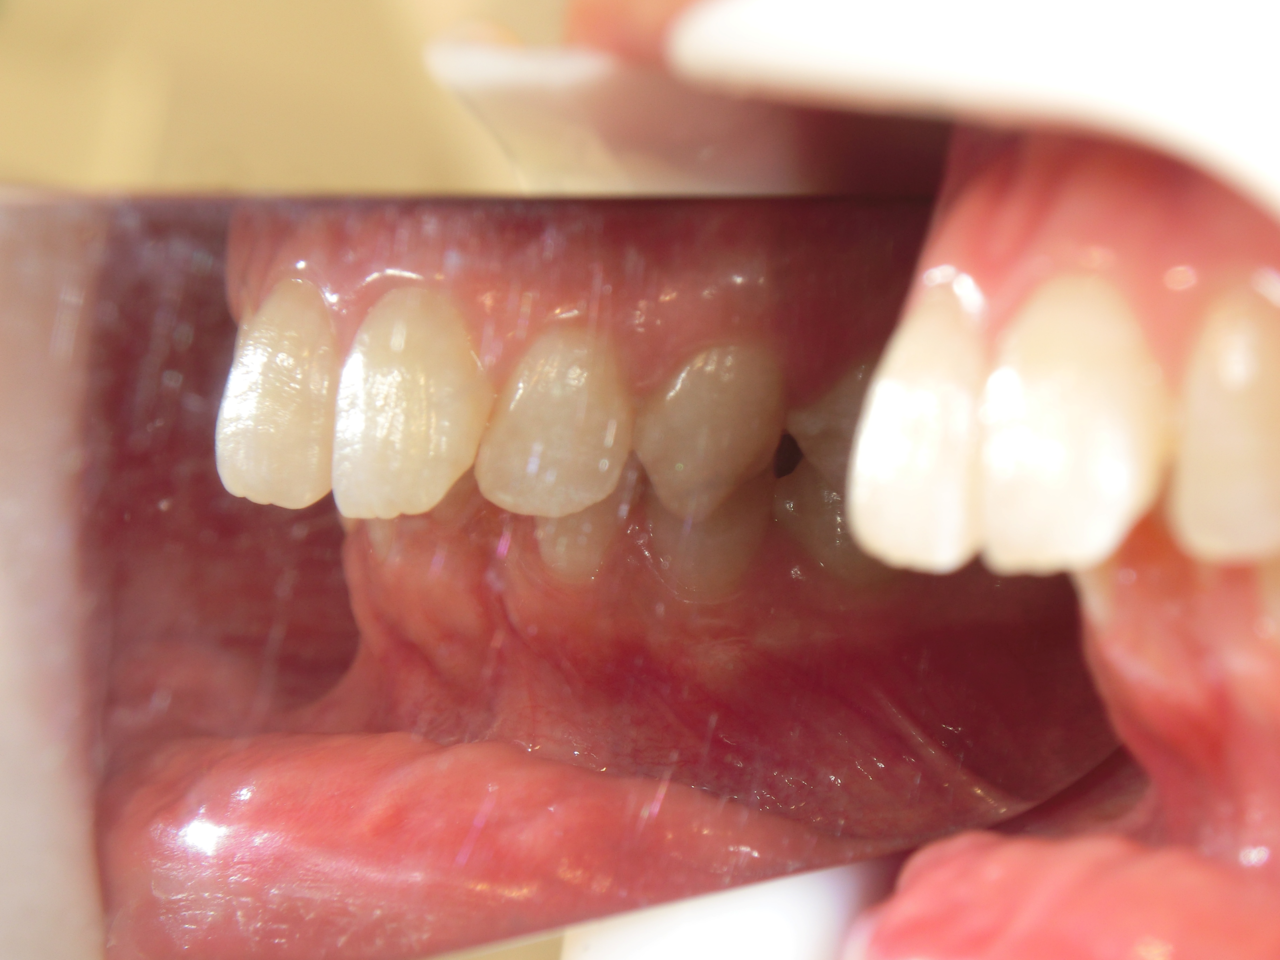

治療前

治療説明 歯科矯正でも目立ちにくい矯正方法であるマウスピース矯正で治療しました

治療期間 2年6か月

治療費用49,8000 円

治療後

治療の副作用(リスク)歯の動き方には個人差があり、予想された治療期間が延長する可能性があります。。マウスピースの使用状況、矯正歯科治療には患者さんの協力が必要であり、それらが治療結果や治療期間に影響します